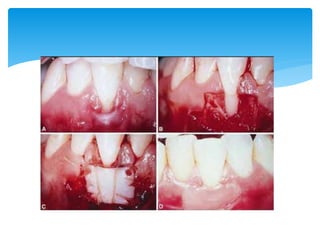

Colgajo desplazado lateralmente..

Este colgajo es de espesor total mucoperiostico, y

puede realizarse de espesor parcial.

 Su objetivo es detener la resecion gingival y restaurar

la encia adherida.

 Este tipo de colgajo es indicado, donde existe una una

resecion gingival adyacente . Donde hay dehiscencias

, fenestraciones y en casos donde el hueso es muy

fino.

Colgajo desplazado lateralmente.. Estecolgajo es de espesor total mucoperiostico, y puede realizarse de espesor parcial.  https://youtu.be/2XE5VAw1j6A

 Su objetivoes detener la resecion gingival y restaurar la encia adherida.  Este tipo de colgajo es indicado, donde existe una una resecion gingival adyacente . Donde hay dehiscencias , fenestraciones y en casos donde el hueso es muy fino. Objetivo